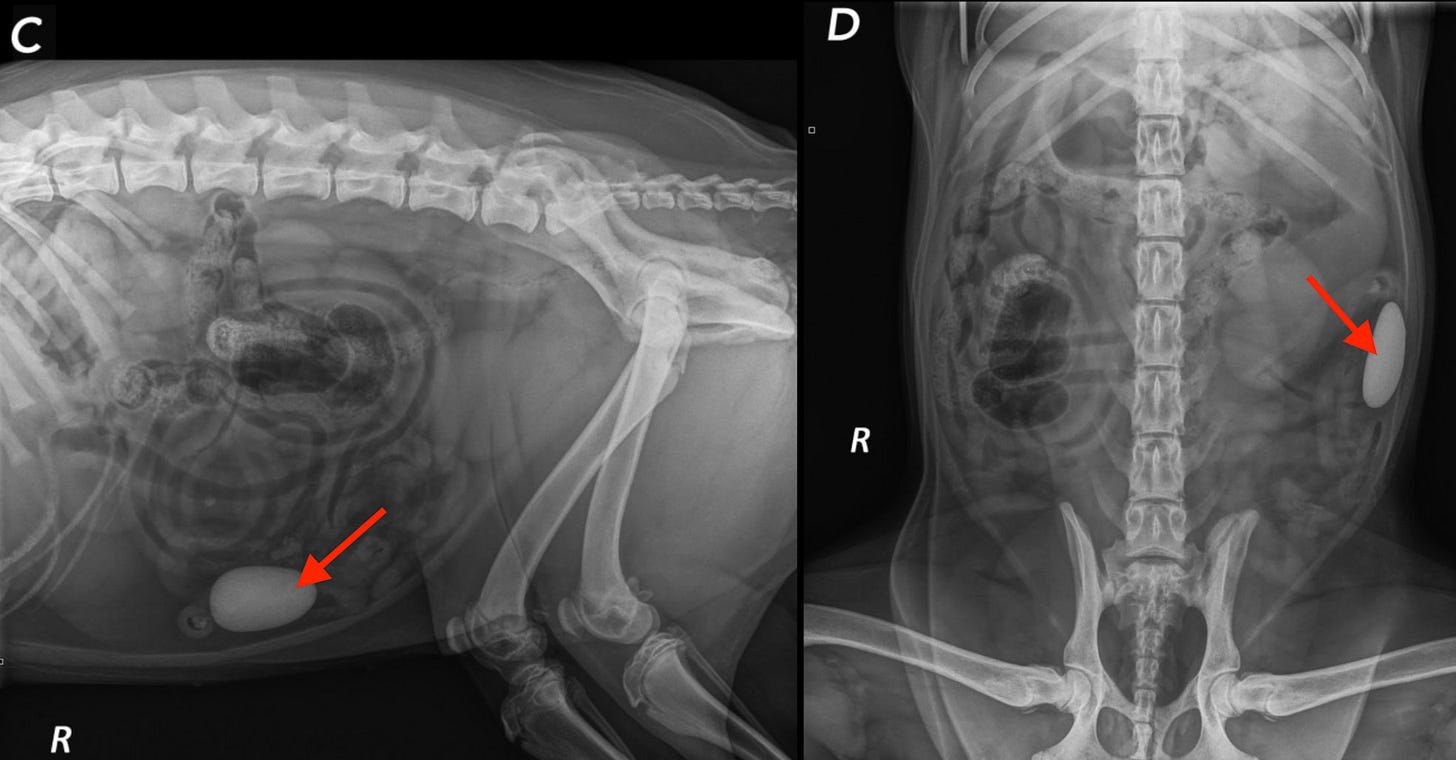

In what might be the craziest example, the authors showed a case where a dog literally ate a rock (red arrows), and one service called it NORMAL!!! Another went off the rails and diagnosed a bunch of crazy nonsense 😱